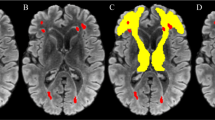

Measurement of WML

The severity of WML for each subject was rated according to the modified Fazekas scale33 or the Age-Related White Matter Changes Scale (ARWMC)34 based on the MRI axial FLAIR sequence or CT. We used the operationalized global Fazekas rating, which has a score ranging from 0 to 335. We also used the operationalized global ARWMC score, with a score ranging from 0 to 334. We defined the presence of moderate-to-severe WML by a global score of ≥ 2 for both Fazekas and ARWMC scale. The Hong Kong community dataset with both Fazekas and ARWMC global ratings showed that the correlation between the scales was high (p < 0.0001; r = 0.943). Both visual rating scales of WML showed good agreement between CT and MRI36.